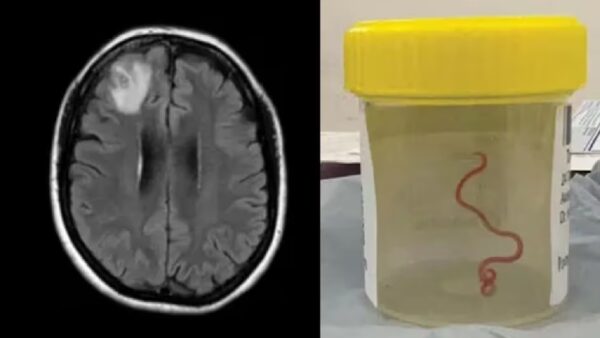

या संपूर्ण प्रकरणावर कॅनबेरा येथील संसर्गजन्य रोग विशेषज्ञ डॉ संजय सेनानायके म्हणाले, न्यूरोसर्जनने शस्त्रक्रिया केली नाही कारण त्यांना महिलेच्या डोक्यात किडा आढळून आला होता. सेनानायक यांनी यानंतर या घटनेची माहिती सर्जनला दिली. तुम्हाला विश्वास बसणार नाही, या महिलेच्या डोक्यात काय आढळले आहे. हा एक किडा असून तो जिवंत असल्याची त्यांनी माहिती दिली होती.

डोक्यात 3 इंच लांबीचा किडा

डॉक्टरांनी दिलेल्या माहितीनूसार, महिलेच्या डोक्यात आढळून आलेला किडा 3 इंच लांब, चमकदार लाल रंगाचा आहे. या किड्याला पॅरासाईट राउडवॉर्म म्हणतात. तर शास्त्रज्ञांमध्ये या किड्याला ओफिडास्कॅरिस रॉबर्टसी म्हणून ओळखले जाते. ही प्रजाती सापांमध्ये आढळते. राउंडवर्मचा हा विशिष्ट प्रकार कार्पेट पायथन्स (अजरग) मध्ये आढळतो,ही एक मोठी प्रजाती आहे. हे ऑस्ट्रेलिया, इंडोनेशिया आणि पापुआ न्यू गिनीमध्ये आढळतो.